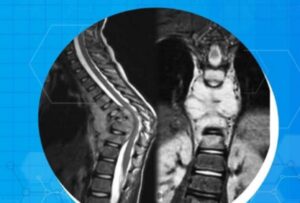

Penegakkan diagnosis menjadi hal utama dalam penanganan TBC Tulang Belakang. Jika terjadi keluhan tsb, maka dilakukan pemeriksaan penunjang seperti pemeriksaan laboratorium, pemeriksaan radiologi seperti rontgen atau x-ray tulang belakang dan pemeriksaan Magnetic Resonance Imaging (MRI) tulang belakang. Selain itu screening pada lingkungan sekitar pasien juga dapat dilakukan untuk mengetahui apakah ada orang-orang disekeliling pasien yang terinfeksi kuman TBC.